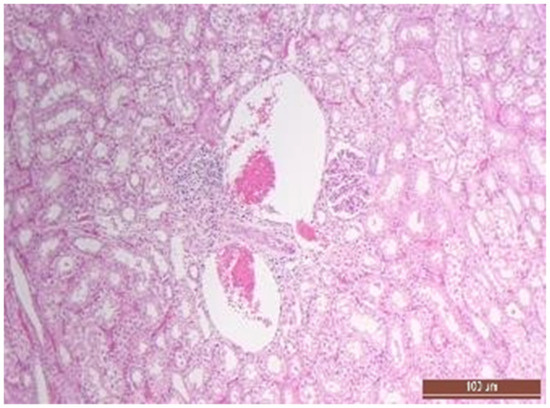

3.4. Pathology of Kidneys